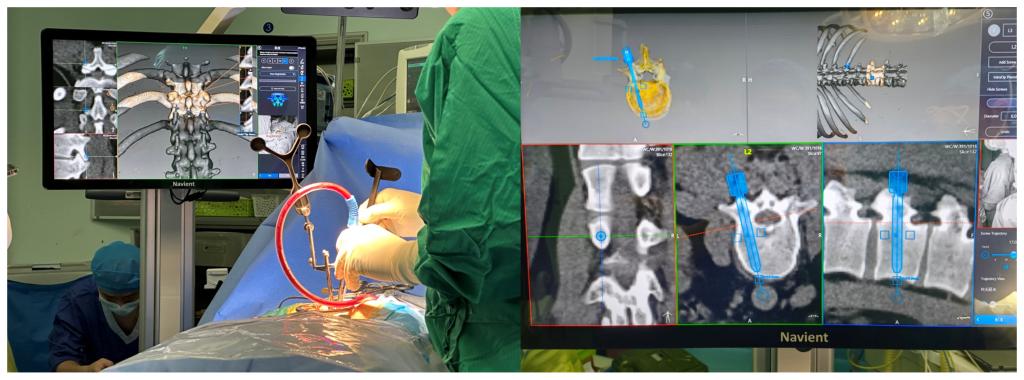

下一步的治疗策略令有着丰富脊柱手术经验的李浩鹏主任和李锋涛教授团队犯了难:胸椎椎管严重狭窄,前方的椎间盘及后方韧带前后夹击,椎管的侵占率达到了90%以上,手术操作稍有不慎非死即瘫;腰椎经过之前两次手术治疗,局部解剖结构早已变得面目全非,而且胶原酶注射后局部瘢痕黏连严重,神经损伤风险陡然提升。面对着年轻小伙子的殷切期待,李浩鹏主任最终决定运用智能化的手段,在导航机器人的辅助下,采用直观定位技术进行置钉减压,使手术更精准、更便捷、更安全。

术前,李锋涛教授团队将采集患者的三维CT数据并将其导入到机器人术前规划系统中,机器人工程师与其配合确定穿刺位置、角度、深度等信息,制定出适合患者本人的个性化手术方案并在术中由机器人予以实施。相较于之前脊柱手术置钉需要反复X线透视来确定螺钉位置,脊柱机器人导航可实现脊柱精确定位,提高置钉的准确性,降低误伤神经、血管的风险,有效减少手术并发症。手术当日,李浩鹏主任,李锋涛副主任医师、王放副研究员和王瑞博士在导航机器人的辅助下,轻松完成原先脊柱手术中风险巨大的椎体植钉过程,随后的椎管减压及神经根松解等步骤一气呵成,有效缩短了手术时间、术中投射次数,大大降低了手术风险。

随着智能化时代的来临,导航机器人的使用使得脊柱外科的手术向着更加精准化、数字化迈进。导航机器人辅助下的手术更加简洁快速高效,术中透视少,手术时间大幅缩短,创伤小,软组织损伤小,下地早,后遗症少,可以满足患者微创和更早下地快速康复的要求。李锋涛副主任医师介绍,“导航系统越来越多的应用于脊柱外科微创手术及复杂疑难手术,如脊柱镜下融合术、经皮椎弓根螺钉植入术、脊柱畸形矫形术及寰枢椎手术中,是精准外科时代为患者带来的福音。”